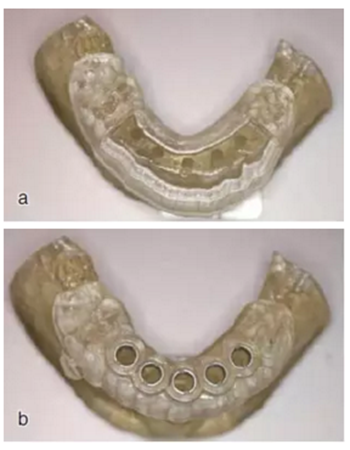

制作導(dǎo)板

根據(jù)種植方案,設(shè)計并加工出截骨導(dǎo)板和種植導(dǎo)板。圖為截骨導(dǎo)板與種植導(dǎo)板實物。

圖16 a.截骨導(dǎo)板;b.種植導(dǎo)板